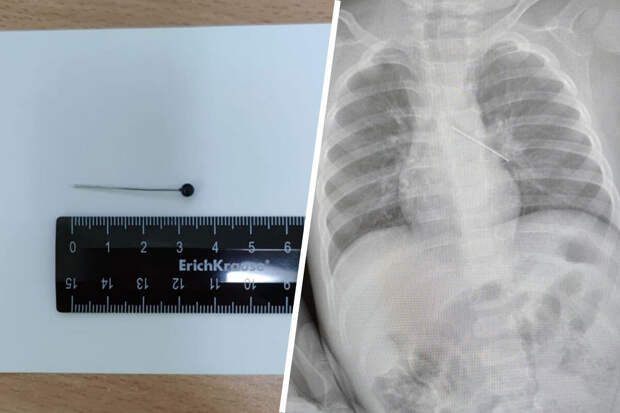

Обследование показало, что инородный предмет зафиксировался в бронхах."Если бы бригада наших высокопрофессиональных специалистов не смогла удалить инородный предмет с помощью бронхоскопа, ребенка пришлось бы передавать торакальным хирургам для проведения большой операции", - пояснила Белоцерковцева.